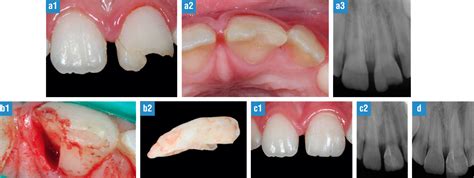

A continuación, se describe el caso de un paciente de 18 años que presentaba una fractura horizontal del tercio medio radicular así como una fractura coronaria simple y otra compleja en la zona de los incisivos superiores. El cuadro se acompañaba de grandes lesiones periapicales y no había sido tratado previamente.

Un paciente de 18 años de edad con dolor y tumefacciones recidivantes en el sector anterosuperior fue remitido a una clínica para su valoración y tratamiento. El paciente no tenía antecedentes patológicos de interés. En la anamnesis odontológica destaca un accidente de bicicleta 8 años atrás que provocó la pérdida de los incisivos centrales y laterales de la dentición permanente. El paciente refirió que unos familiares le llevaron a urgencias de un centro hospitalario para el tratamiento de una herida incisa en piel y mucosa del labio superior. Se procedió a la sutura del labio superior, pero los dientes fracturados no se trataron. Además, el paciente no acudió en ningún momento a una consulta dental a pesar de que en los últimos dos años había observado una fístula que daba síntomas ocasionales.

En la primera exploración no se evidenciaron ni adenopatías, ni parestesias ni déficits motores. En el maxilar se observó una fractura coronaria complicada del incisivo central derecho y una fractura coronaria simple del incisivo lateral izquierdo. Se diagnosticaron además hiperemias y tumefacciones con orificio de salida fistular en vestibular en la zona apical de ambos dientes. Las tumefacciones eran fijas y no mostraban signos de fluctuación. Únicamente el incisivo central izquierdo mostró una reacción normal a la prueba de sensibilidad con nieve carbónica y con un pulpovitalómetro, mientras que los otros tres incisivos superiores no respondieron.

Los dos dientes con fractura coronaria (incisivo central derecho e incisivo lateral izquierdo) mostraron además sensibilidad a la palpación y a la percusión. Ninguno de los incisivos presentaba movilidad.

En la radiografía se observaron dos lesiones radiolúcidas independientes. Una de ellas se localizaba en la zona periapical de los incisivos central y lateral derechos y la otra lesión se hallaba en la zona periapical de los incisivos central y lateral izquierdos. En el tercio medio del incisivo central izquierdo se detectó además una fractura radicular horizontal. Los fragmentos estaban separados por una línea radiolúcida y los bordes fracturarios mostraban un aspecto redondeado a nivel periapical. Desde el punto de vista clínico, el diente no era móvil ni mostró sensibilidad a la percusión. Según la clasificación de Andreasen y Andreasen parecía haber tenido lugar un proceso curativo con formación de tejido conjuntivo entre los segmentos radiculares.

Se constató la buena evolución del proceso de cicatrización al retirar la sutura una semana después de la intervención. Las tumefacciones eran mínimas, el trayecto fistuloso estaba en fase de regresión y la cicatrización de los tejidos blandos evolucionaba satisfactoriamente. Sin embargo, como consecuencia de la pérdida de sustancia los dientes perdieron inserción y se volvieron móviles. Con objeto de estabilizarlos se colocó una férula durante un período inicial de un mes. La férula constaba de un alambre de acero inoxidable fijado con resina composite.

En la visita de control al cabo de un mes los incisivos seguían mostrando movilidad, lo que obligó a mantener la fijación durante otros tres meses. En esta sesión se restauró el incisivo central derecho con composite grabado al ácido (Grandio). La movilidad de los dientes se había normalizado una vez retirada la férula en la visita de control a los cuatro meses. Se restauró también el incisivo lateral izquierdo con un resina composite grabado al ácido (Grandio).

En la visita de control al cabo de seis meses los dientes estaban asintomáticos y mostraban signos de curación ósea periapical. Al cabo de 12 meses, el proceso de curación ósea periapical había llegado prácticamente a su fin. Al mismo tiempo se observó una encía perfectamente curada y con un contorno bien perfilado.